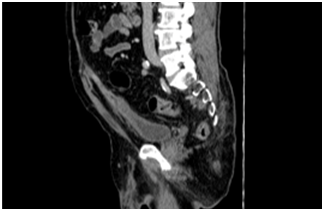

We report a case of a 72 years-old male patient who had history of previous purulent drainage through the belly bottom during the last 18 months. He had undergone to open appendectomy 14 years ago. During these episodes local treatment with topical antibiotics was performed with partial resolution. He came to the clinical office complaining about purulent discharge through the umbilicus again. CT showed a 4 cm fluid collection located in the infraumbilical middle line, communicating with the belly bottom (Figure 1 & 2). The patient accepted to undergo surgery. We performed a laparoscopic approach. Before portal placement and pneumoperitoneum we dissected the infected area inside the umbilicus, sutured with 2-0 Vycril® and left the specimen inside the abdominal cavity. Figure 3 demonstrates our standard ports placement. After this, we placed a 10 mm port, 8 cm above the belly bottom and started the pneumoperitoneum. The camera was placed in this trocar. Another two 5 mm ports were placed lateral to the rectus abdominis, one for a grasper and the other for scissor (Figure 4) Adhesions were perceived during cavity inspection.. We dissected the urachus and. a retained suture material with intense inflammatory reaction was identified (Figure 5). Bladder resection was not needed. The surgical specimen was removed through a 5 mm portal. Fascia was sutured with 0 Vycril®. Estimated blood loss was not quantified. Operative time was 94 min.Patient was discharged 24 h after the procedure and no early or late complications were reported after 60 days of follow-up. Pathology report demonstrated fibrotic connective tissue with chronic inflammation and foreign body granuloma in a 6.0 x 2.0 x 1.8 cm specimen.

Figure 4 Dissection of suspected infected urachusremnat.

Figure 5 Retained suture material with intense inflammatory reaction.